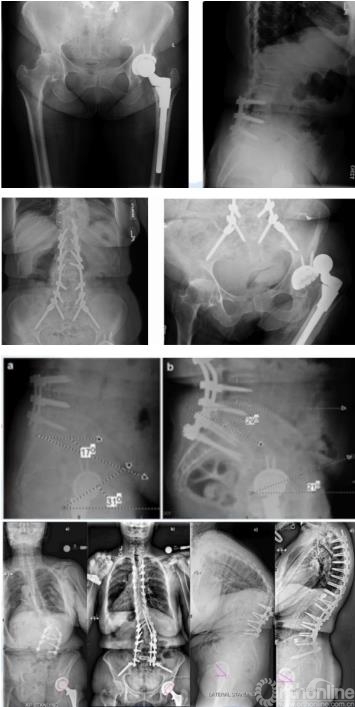

腰椎退变与融合对THA的影响

术前有腰椎融合史,同样会对THA术后关节稳定性产生影响。1项包含1456898例人工关节病例的荟萃分析显示,初始腰椎脊柱融合术增加THA的脱位和翻修风险。另1项配对分析也显示,融合节段越多,与假体相关并发症发生风险也越高。

图6 多例病例显示脊柱-骨盆固定后骨盆前倾,髋臼前倾角变小

脊柱-骨盆力线不良的患者髋臼假体过度前倾的患病率高,而且THA术后脊柱矢状面矫正导致髋臼前倾角减小,可能影响稳定性。脊柱融合术前倾的变化与骨盆盆倾斜的变化幅度甚至接近1:1。

强直性脊柱炎对THA的影响

强直性脊柱炎(AS)患者脊柱矢状面的畸形,会导致胸椎后凸增大,腰椎前凸减小,这样的生理结构导致患者站立位骨盆出现过度后倾。系统综述也显示,这样的后倾导致髋臼前倾角异常增大。骨盆后倾,髋关节前倾角增大也是THA术后脱位和翻修的主要原因。因此针对AS患者,术前需要设计髋臼假体位置。

图7 AS引起THA术后脱位病例

手术时可根据后倾角度调整髋臼假体置入角度,减小外展与前倾角,防止术后脱位,增加站立位髋关节稳定性的同时,减少了假体与骨的接触面积,以适应变化的脊柱-骨盆力线,避免术后出现髋臼假体过度前倾,以及站立位时发生后方撞击、前方不稳甚至前脱位等并发症。对于合并脊柱后凸畸形的AS患者,除非畸形过于严重,应首选脊柱矫形术,再行THA。